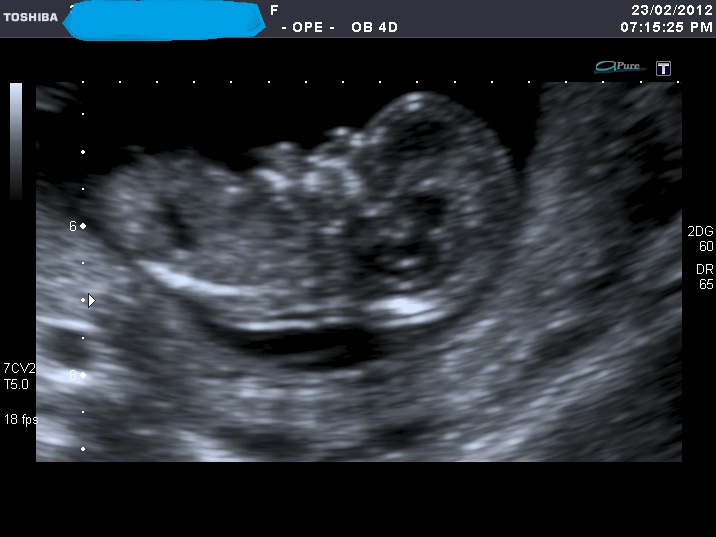

I'm sorry for spaming again with my nub shots, but now when I look at u/s pics I'm not sure I can a see a nub at all????

If you can see it, please enlighten me where to look. Also I think scull looks girly on some pics and boyish on the others.

I was 12 weeks, measuring 12 weeks 5 days